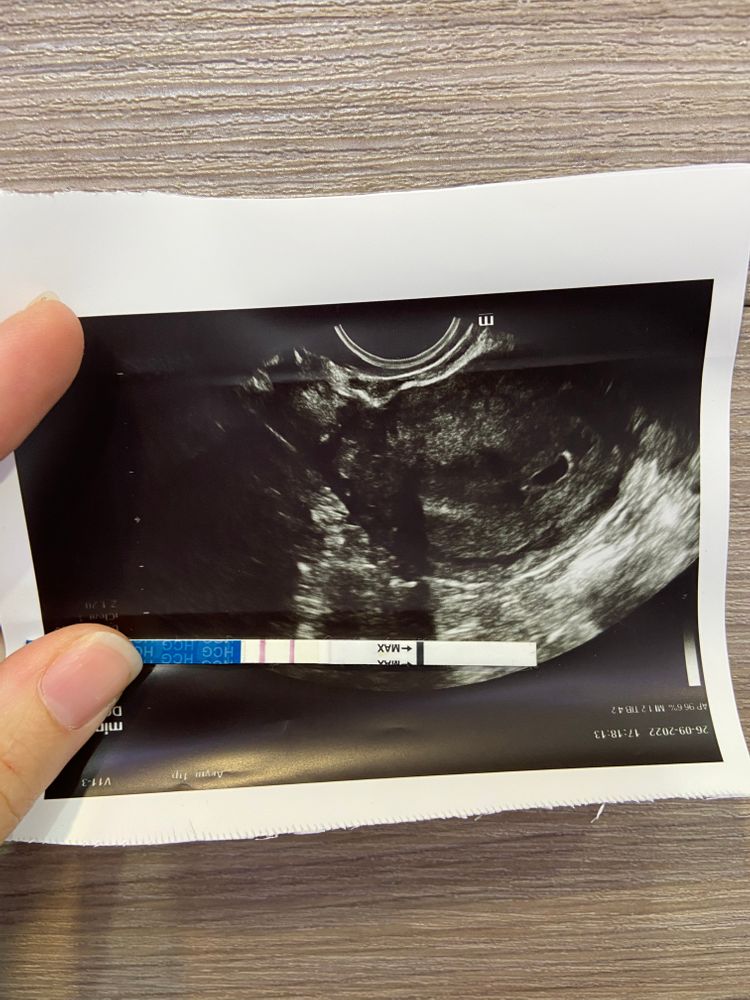

Растёт бусинка ❤️

Сходила на узи ❤️ все хорошо , малыш растёт )) к 7 неделям пойду в жк , раньше думаю нет смысла )) спросила про боль в левом яичнике , сказали что овуляция была слева , оттуда и неприятные ощущения. В след раз надеюсь уже увижу крошку малыша ❤️